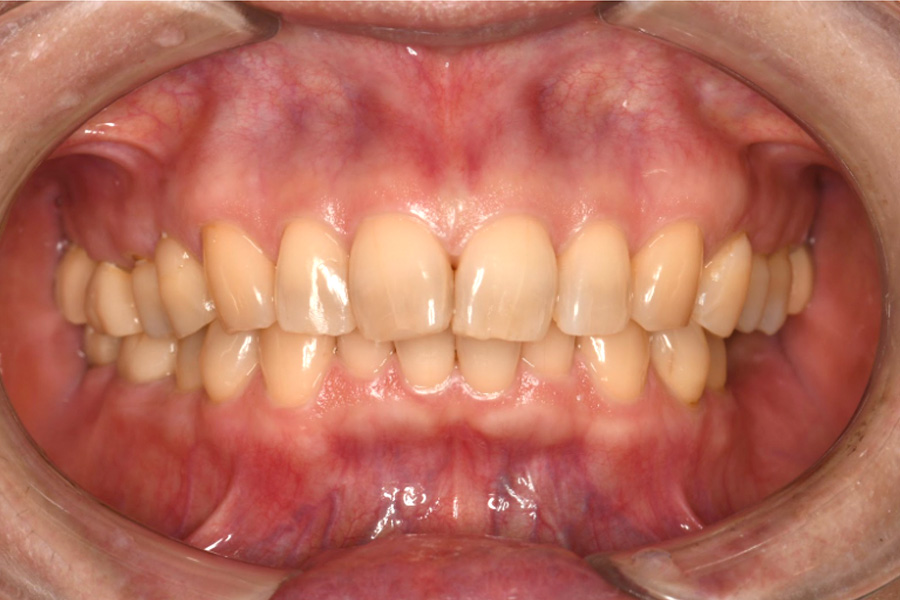

治療前

(口腔内写真)

【口腔内写真】正面から見たお口の状態

歯ぐきの表面には、過剰な圧力から歯を支えようとして地盤が肥大化した「骨隆起」がデコボコと隆起しています。また、頬の内側には頬圧痕(きょうあっこん)と呼ばれる白い筋が確認でき、これは就寝中だけでなく、日中も無意識に強い力で食いしばり(クレンチング)を続けている決定的な証拠です。

本来は尖っているはずの犬歯は鋭利さを失って平らにすり減り、前歯の表面には過酷な負荷による構造疲労で生じた「縦方向のヒビ(クラック)」が無数に入っています。これらはお口全体が設計限界を超えた「オーバーロード」の状態にあり、いつ致命的な破壊が起きてもおかしくない危険なサインです。